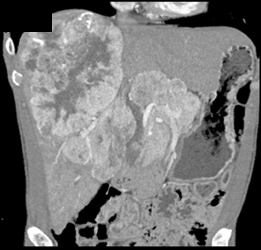

Carcinoid Metastatic to Liver